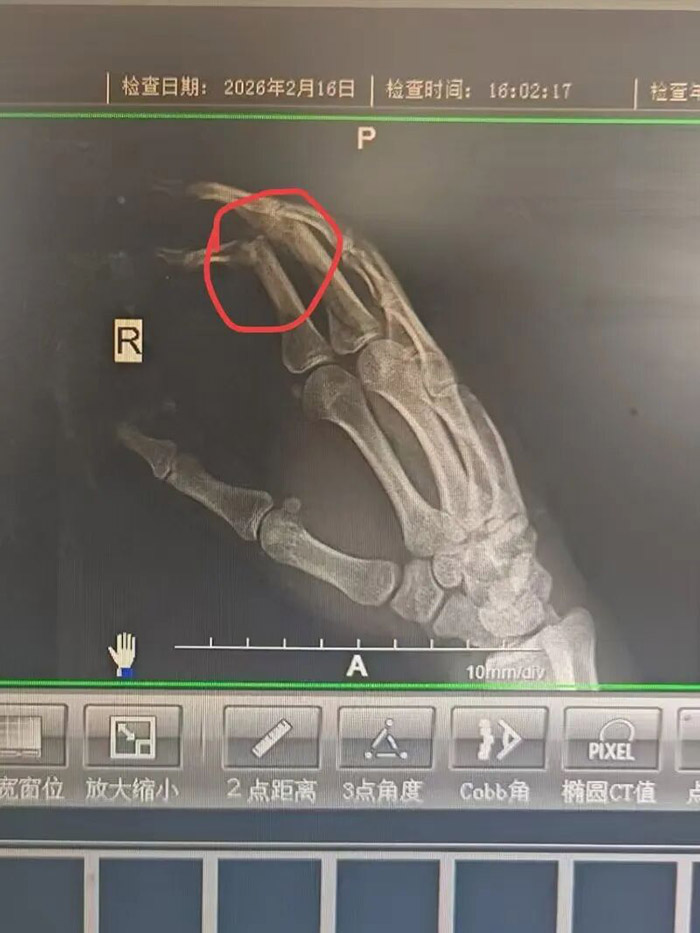

2月16日傍晚,我院急诊科紧急转运来一名30余岁男性外伤患者。患者在家中整理物品时,不慎被破碎玻璃严重划伤右手,手背及四根手指创口较深,其中食指伤情危重,出现肌腱断裂、关节脱位,肢体功能面临严重威胁,情况万分危急。

时间就是功能,时间就是未来。接诊后,骨科值班医生宋志立即带领医护团队启动急诊创伤救治流程,全员快速响应、无缝衔接,第一时间为患者完善术前检查、彻底清创消毒,并根据伤情精准制定手术方案,随即开展肌腱吻合修复术+关节复位固定术。

医学上,手指肌腱断裂合并关节脱位的救治黄金时间很短。若延误手术,断裂肌腱会迅速挛缩、粘连,导致手指屈伸功能永久性丧失;脱位关节拖延复位,则会造成关节畸形、慢性疼痛,极大概率遗留终身残疾,直接影响患者日后工作与生活。

与时间赛跑,为功能护航。手术台上,骨科医护团队凝神聚力、精细操作,在狭小的手术区域里精准吻合断裂肌腱、稳妥复位固定脱位关节,每一个动作严谨规范,每一步操作精益求精,全力为患者争取最佳预后,最大限度降低后遗症风险。